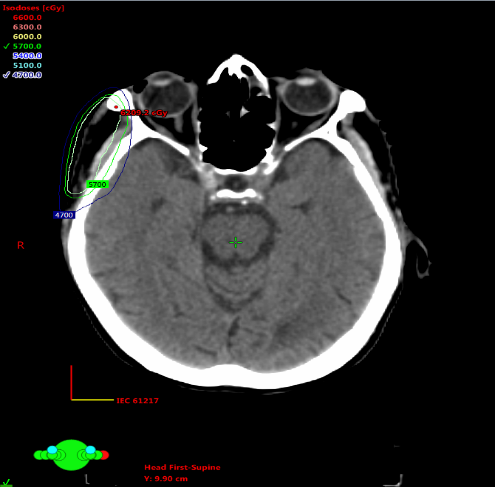

The original lesion was surgically removed in its entirety. The histopathological examination (HPE) revealed a 2.5 x 2 x 1 cm tumor in the dermis, an extensive pool of extracellular mucin, and floating clusters of tumor cells with mild to moderate nuclear pleomorphism and eosinophilic cytoplasm, histological features consistent with mucinous adenocarcinoma (Figures 1a and 1b). The deep margin of resection was positive. A PET CT scan was performed to rule out the main and additional locations, which were normal. The patient denied additional revision surgery or FNAC from the neck node; hence, the multimodality tumor board agreed on adjuvant radiation treatment. The patient received 60 Gy in 25 fractions to the tumor bed with margins and 50 Gy in 25 fractions to the preauricular and right level II nodal regions while respecting organ at risk (OAR) tolerance (Figure 2). The patient handled radiation well, requiring no treatment pauses and experiencing just grade II acute cutaneous toxicity. The patient was scheduled for clinical follow-up. After 16 months of follow-up, there is no clinical evidence of a local or distant recurrence, and the patient lives a normal life.

Figure 2. IMRT plan of Case 1 showing isodose coverage of tumor bed